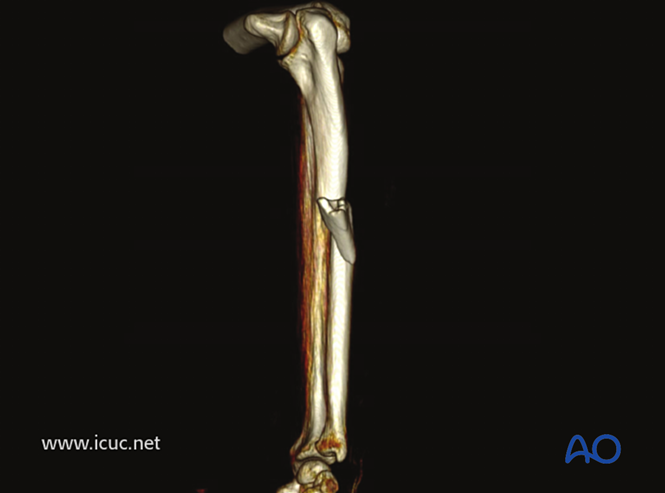

三维CT图像。

49周时的正位和侧位影像。